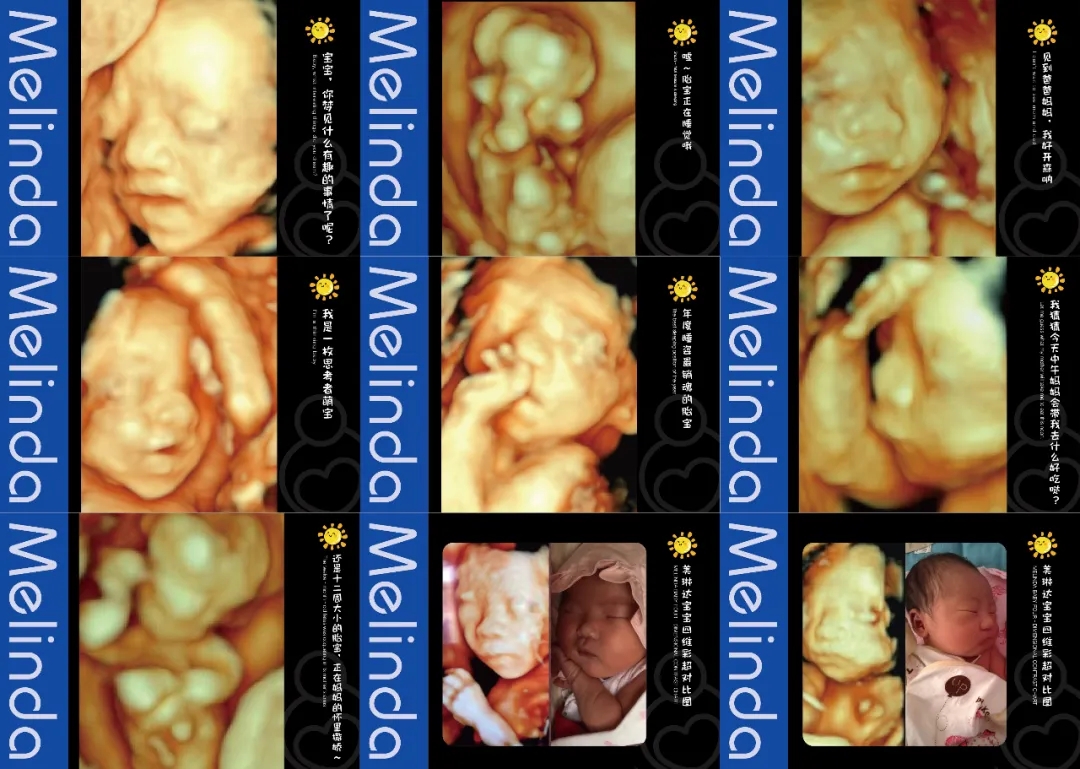

(美琳达四维宝宝照片)

为给孕妈及女性患者提供舒适的就诊环境,每间超声诊室里均设置适宜观看的高清电视屏幕,双屏互动模式,检查时孕妈及女性可以清晰看见医生操作。在不影响检查情况下,医生会就孕妈及女性患者关心问题细致性讲解。检查床旁放置舒适纯皮沙发,支持家属陪伴检查。如若是做四维彩超的孕产家庭,准爸在陪伴产检的过程中,还可以拿手机拍摄记录,美琳达也会提供胎儿写真照片,让您体会不一样的惊喜和感动。